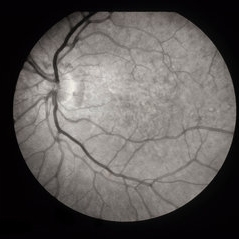

ARMD

Jan 13 2014 by David Callanan, MD

HM OU marked RPE atrophy, 63-year-old female.

Condition/keywords: age-related macular degeneration (AMD)